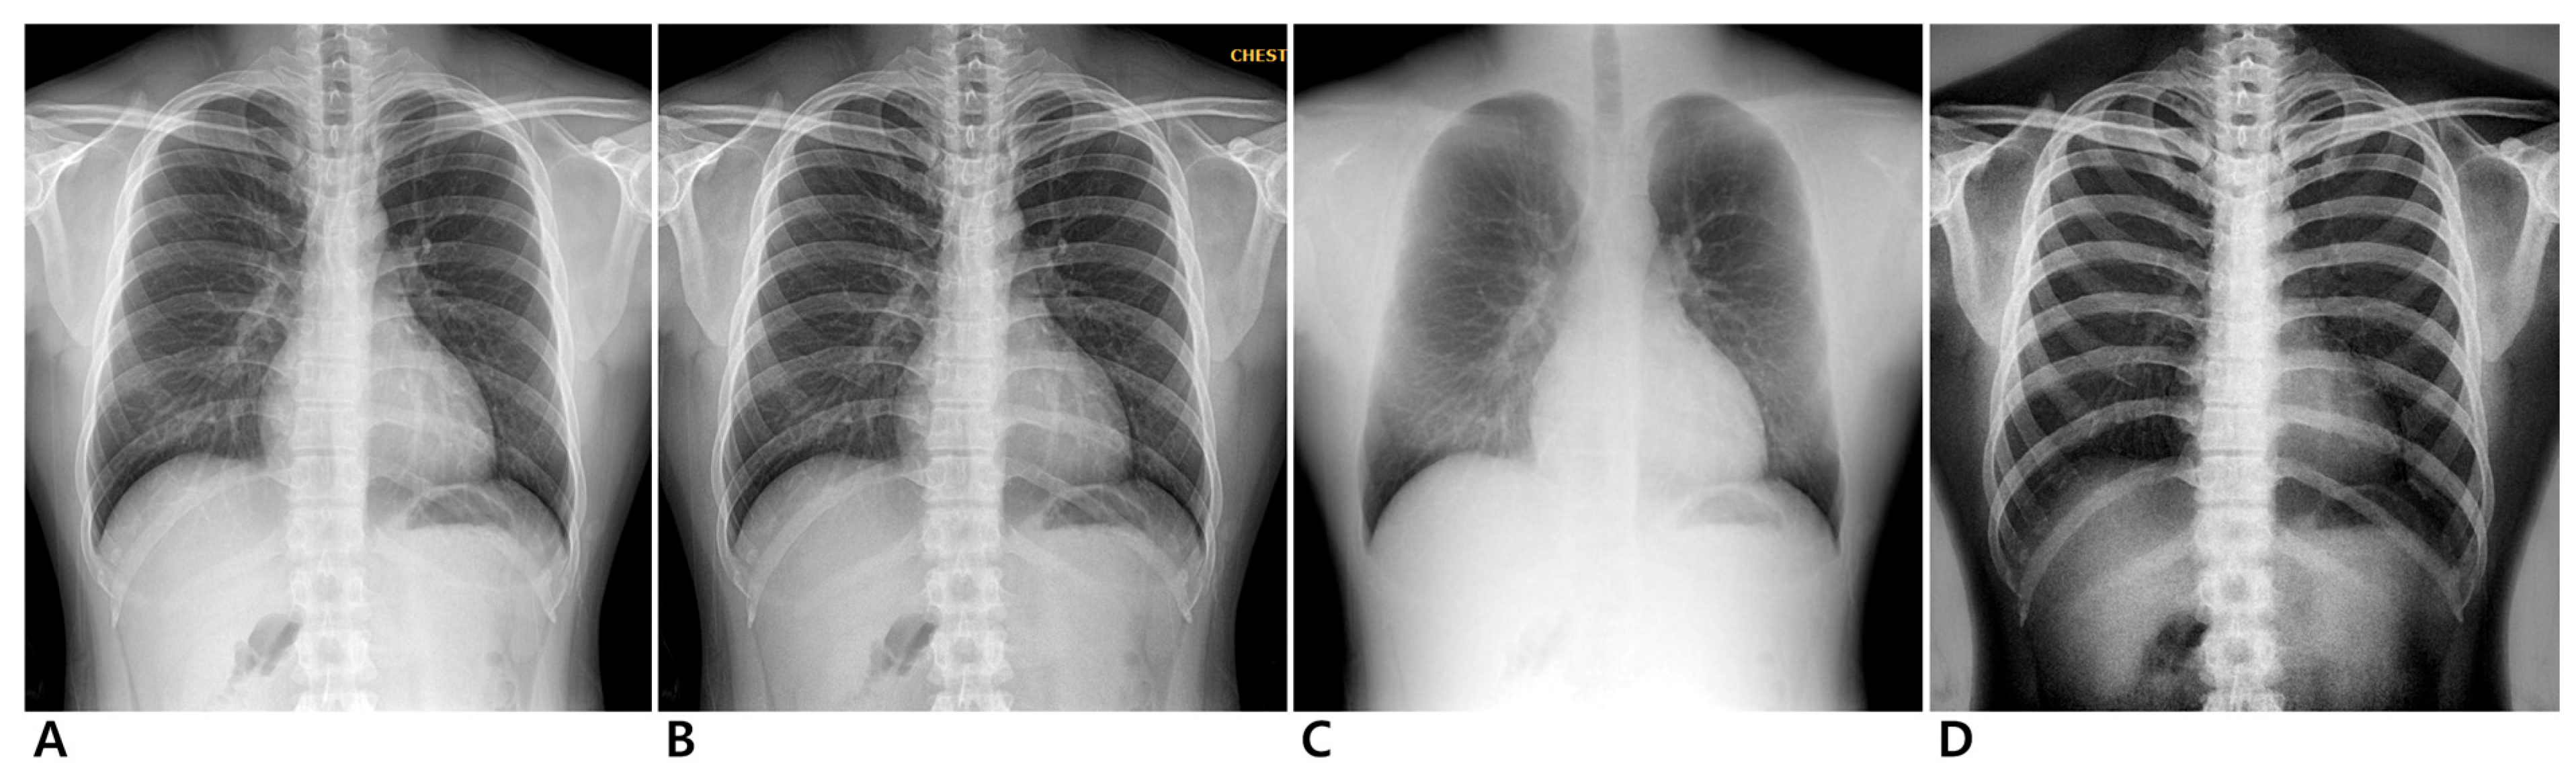

3.2.1. Conventional Standard vs. Enhanced Standard Images

3.2.2. Conventional Standard vs. Soft-Tissue-Selective Images

3.2.3. Conventional Standard vs. Bone-Selective Images